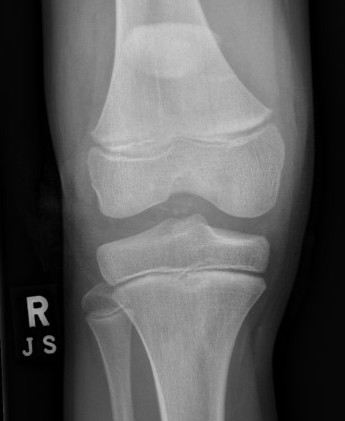

Xray

Patella alta / high riding patella

Very small bony fragment

Minimally displaced patella sleeve fracture